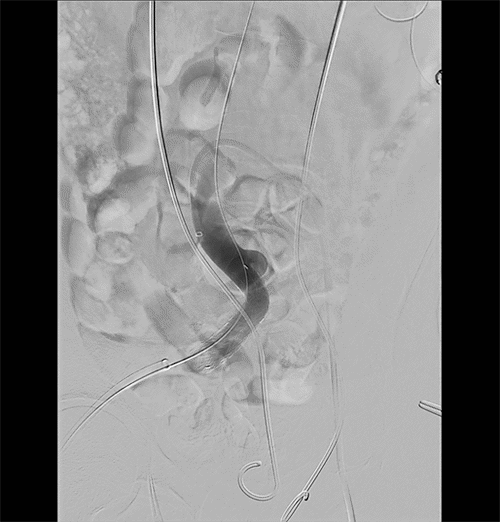

A 63-year-old male with a history of recurrent rectal cancer with metastases, abdominoperineal resection, chemoradiation, deep vein thrombosis on apixaban, pancytopenia, and retroperitoneal fibrosis with ureteral stents presented to the emergency department with fatigue. He had hematuria for ten months, attributed to urinary tract infections (UTIs). On exam, he was hypotensive, with abdominal scars, a parastomal hernia, and hematuria in his urinary catheter. His hemoglobin was 8.3g/dL from a baseline of 9.0g/dL, and his urinalysis demonstrated pyuria and later grew Enterococcus. The critical care team admitted him to the intensive care unit on norepinephrine with suspected urosepsis. His hypotension resolved after resuscitation and treatment with vancomycin, cefepime, and metronidazole. His fatigue and hematuria persisted, and he had a non-contrast CT demonstrating hydronephrosis. He underwent a ureteral stent exchange, but he developed bleeding from the right ureteral orifice during the procedure. This insult resulted in tachycardia, hypotension, and a drop in hemoglobin from 7.6g/dL to 6.7g/dL, requiring a packed red blood cell (PRBC) transfusion. At this point, a fistula was suspected but not confirmed. He had a CT angiogram (CTA), which demonstrated a thrombus in the right ureter, contrast in the renal pelvis bilaterally from his cystogram, and hydronephrosis bilaterally; however, he had no extravasation of contrast. An angiography was planned for later in the week. A few days later, he received nephrostomies for persistent hydronephrosis. He developed bleeding again and required two units of PRBCs for a hemoglobin of 6.4g/dL with an appropriate response of 8.3g/dL. He stabilized before going to the endovascular suite the next day. Pelvic angiography identified a fistula between the ureter and the right external iliac artery (Figure 1). A 16 mm × 14 mm × 7 cm Gore iliac limb extension was placed without jailing the hypogastric (Figure 2). He no longer had bleeding from his urethra. He was discharged on aspirin and amoxicillin clavulanate at the recommendation of an infectious disease consult based on a history of UTIs. Unfortunately, this patient passed a month later from unknown causes, and there was no follow-up in that interval.

Figure 1. Ureteroarterial Fistula. Published with Permission